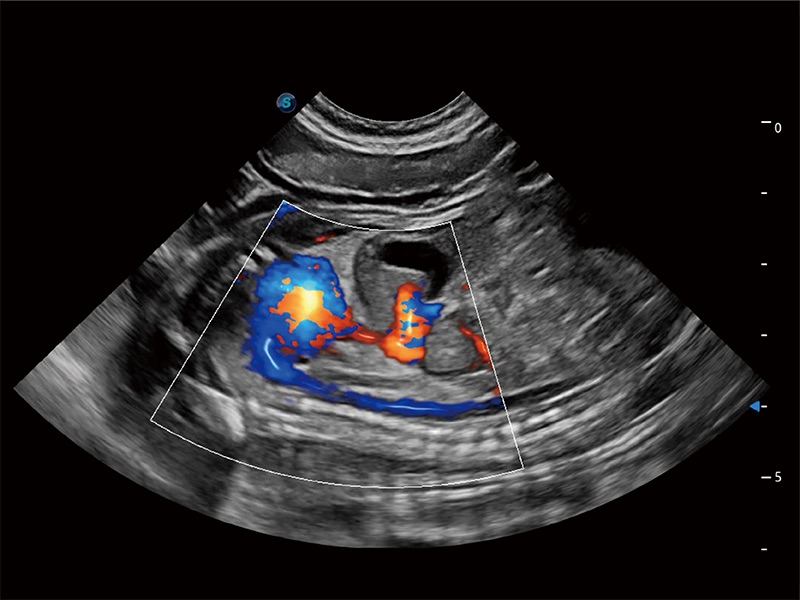

• Micro F 显微血流成像

极大提升超低速微细血流的检出能力,同时更精准地滤除软组织和超声信号,为兽用医生提供以往无法通过常规血流获得的疾病诊断信息。

(犬)肾脏显微血流